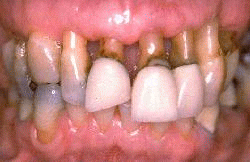

Esta imagen demuestra la condición después de 10 años. Las coronas anteriores se han rehecho. El paciente tiene una línea de la sonrisa baja y las líneas de preparación supragingival no perturban su estética. Ella ha mantenido un excelente control de placa bacteriana y no se obseva signos de enfermedad periodontal. La abrasión ocasionada por el cepillado dental ha aumentado. Ella acostumbra usar un cepillo suave y pasta dental no abrasiva para reducir el desgaste dental por el cepillado diario.